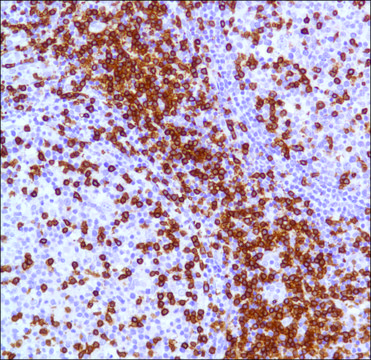

This antibody reacts with the intracytoplasmic portion of the CD3 antigen expressed by T cells. It stains human T cells in both the cortex and medulla of the thymus and in peripheral lymphoid tissues. This antibody is suitable for staining normal and neoplastic T cells in formalin-fixed, paraffin-embedded tissues.

Vikrant Rai et al.

Scientific reports, 10(1), 15167-15167 (2020-09-18)

Cells of the immune system are present in the adult cochlea and respond to damage caused by noise exposure. However, the types of immune cells involved and their locations within the cochlea are unclear. We used flow cytometry and immunostaining